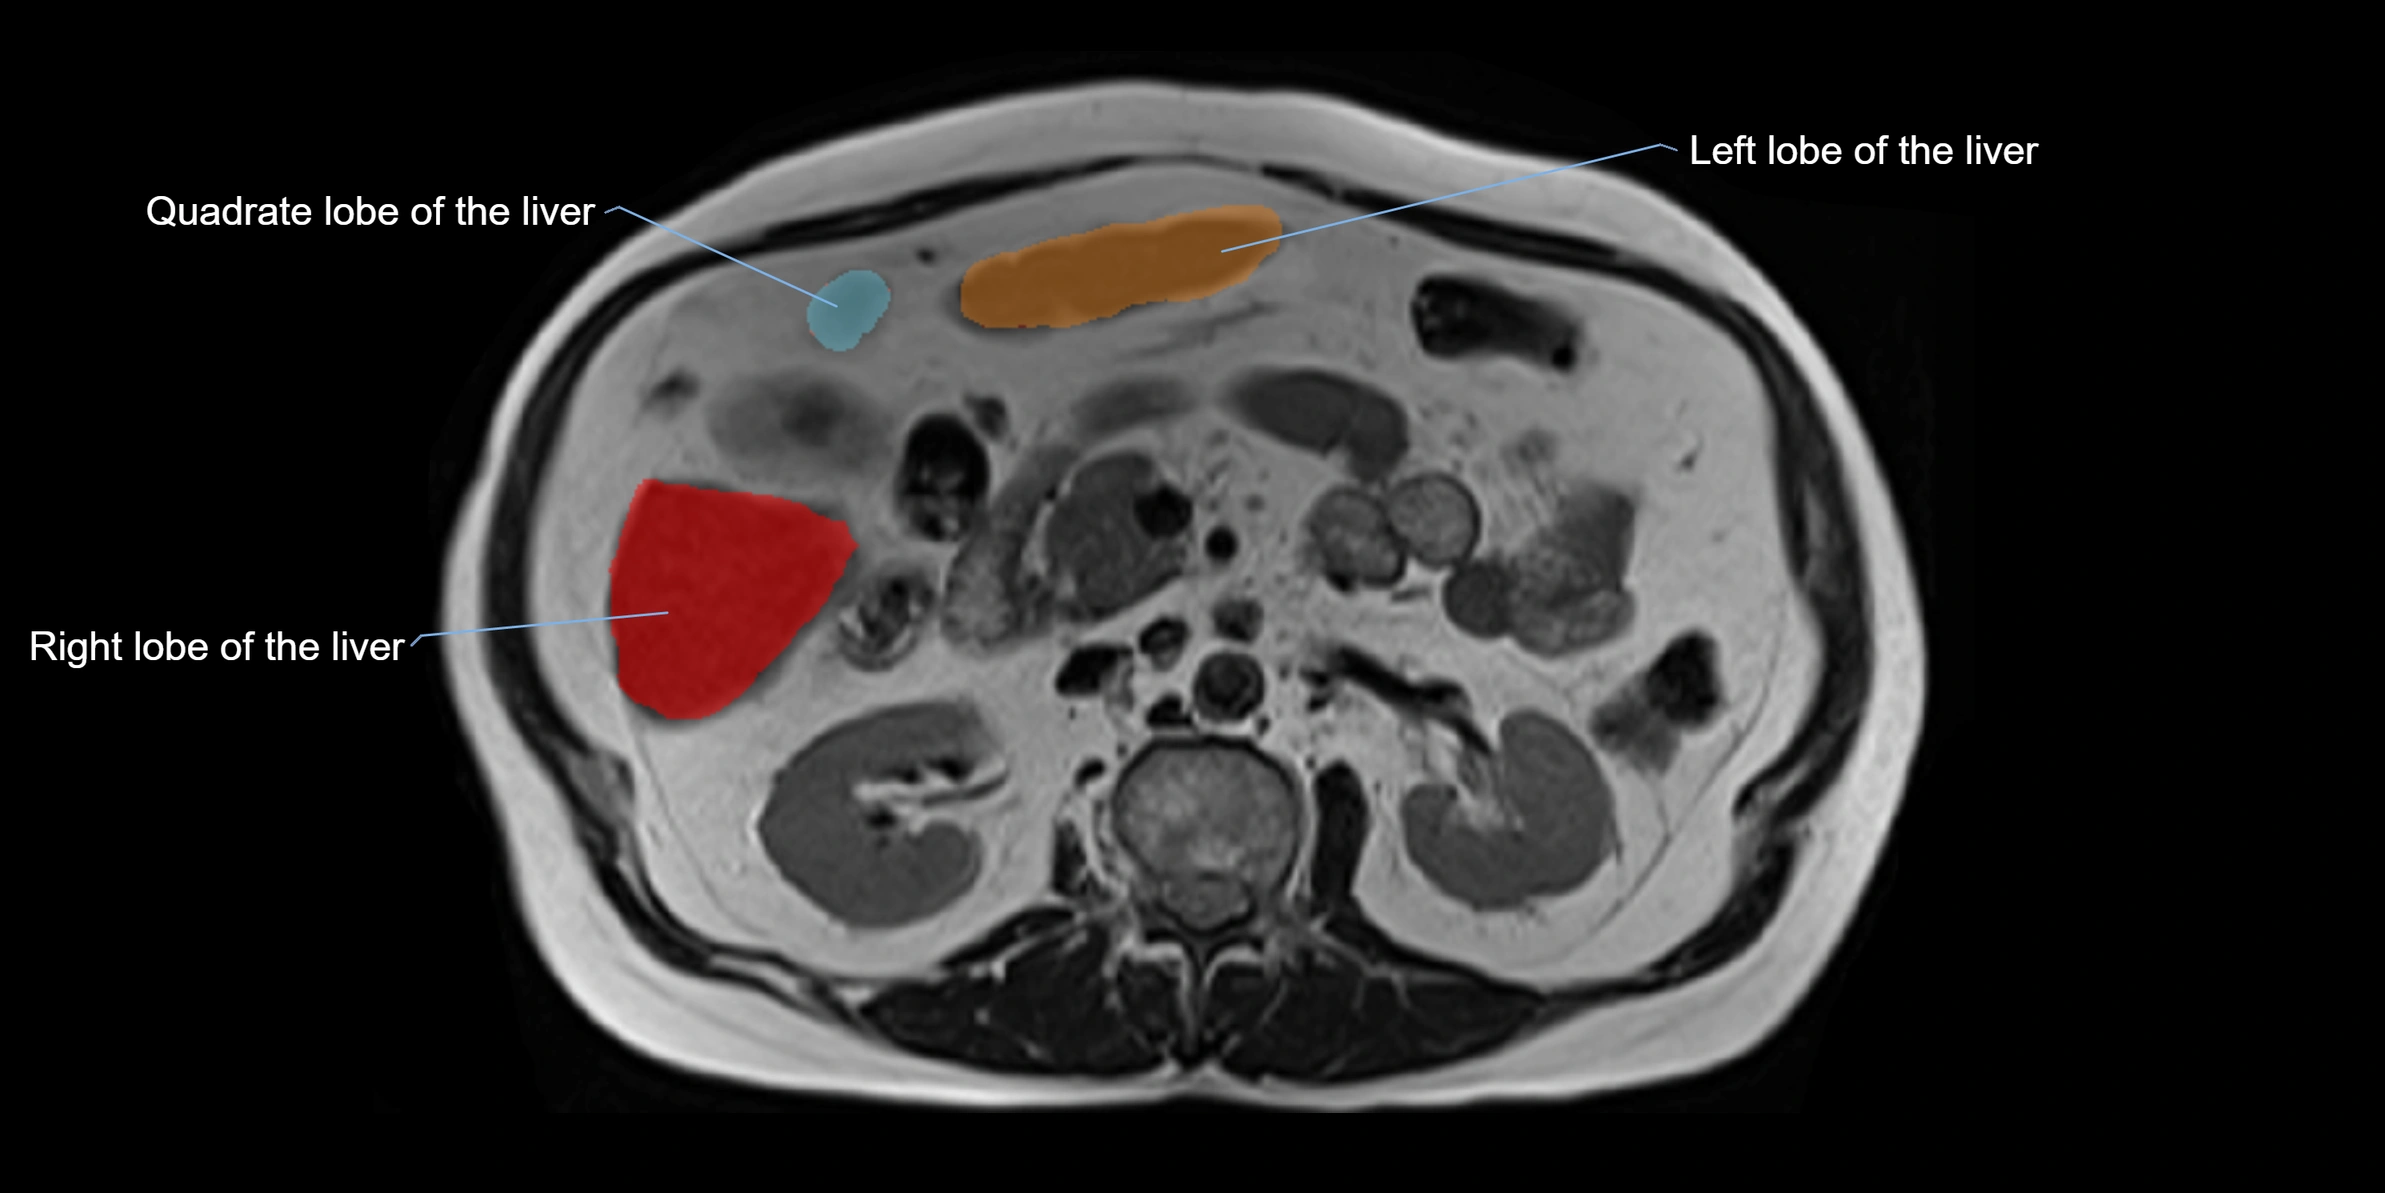

The caudate lobe of the liver is a distinct anatomical subdivision of the liver, designated as segment I in Couinaud’s classification. It lies on the posterior surface of the liver, between the fissure for the ligamentum venosum (left boundary) and the groove for the inferior vena cava (IVC) (right boundary). Superiorly, it is related to the posterior liver surface, and inferiorly it is separated from the left lobe by the porta hepatis.

The caudate lobe is unique because it receives dual portal venous and arterial inflow from both the right and left portal veins and hepatic arteries. It also has independent venous drainage directly into the IVC via multiple small hepatic veins, unlike other lobes that drain through the three main hepatic veins.

This anatomical autonomy makes the caudate lobe especially significant in liver surgery, transplantation, and hepatic venous outflow obstruction syndromes (e.g., Budd–Chiari syndrome). Enlargement of the caudate lobe is a characteristic imaging feature in chronic liver disease and cirrhosis.